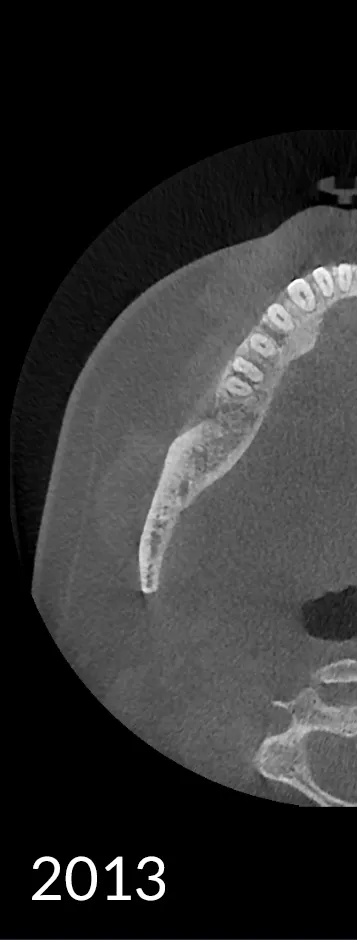

HDX CYOPTIX is our advanced imaging solution designed to deliver exceptional clarity and precision. As a continuously evolving software technology, CYOPTIX enhances image contrast and detail, supporting accurate diagnostics across various applications.

Since its inception, CYOPTIX has undergone continuous development. Our state-of-the-art image reconstruction algorithm now identifies the optimal value for each voxel, dramatically enhancing both contrast and sharpness for clearer, more reliable diagnostic outcomes.